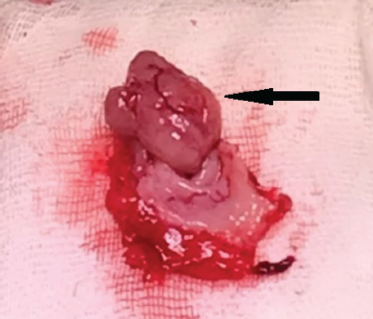

Сформулирован клинический диагноз: «Аденокарцинома правого мочеточника. Правосторонний гепатоколоптоз, осложненный спаечной двуствольной деформацией ободочной кишки, хроническим аппендицитом, запорами». 23.10.2018 произведена комбинированная (симультанная) операция: нефруретерэктомия справа, рассечение спаек брюшной полости, устранение двуствольной деформации ободочной кишки, аппендэктомия, правосторонняя колопексия, фиксация правого края печени. Первым этапом произведена нефруретерэктомия. Мочеточник в верхней трети утолщен до 8–9 мм в диаметре, пальпаторно очень плотный. Нижерасположенная часть мочеточника не изменена. На разрезе стенка мочеточника в верхней трети циркулярно утолщена, белесоватого цвета, без ворсин. Просвет мочеточника резко сужен (рис. 4). Увеличенных лимфоузлов в забрюшинном пространстве не обнаружено. Вскрыта брюшная полость. Выявлен выраженный спаечный процесс в правой ее половине. Большой сальник припаян к восходящей ободочной кишке на всем ее протяжении. Начальный отдел поперечной ободочной кишки спаян с восходящей кишкой на протяжении 10–12 см по типу «двустволки». Восходящая кишка имеет общую брыжейку с подвздошной кишкой. Выражена частая гаустрация восходящего отдела ободочной кишки, что указывает на его избыточную ортостатическую смещаемость. Червеобразный отросток расположен ретроцекально, утолщен до 8 мм, содержит несколько каловых камней. Печень чрезмерно подвижна правым краем, коронарная связка неровная (вероятно, результат травмы при падении с высоты). Произведено рассечение сращений, двуствольная деформация устранена, правый изгиб ободочной кишки фиксирован к задней париетальной брюшине в анатомически правильном положении, выполнены аппендэктомия и фиксация правого края печени путем реконструкции правой треугольной связки. Послеоперационный период протекал гладко, болевой синдром исчез, нормализовался стул. Гистологически подтверждена аденокарцинома мочеточника (Т2N0M0). В червеобразном отростке — хроническое воспаление.

Рис. 4. Пациент З., 68 лет. Макропрепарат удаленного мочеточника. В верхней трети видно утолщение мочеточника, ниже мочеточник не изменен

Fig. 4. Patient Z., age 68. Macropreparation of a removed ureter. Ureteral thickening is visible in the upper third, below the ureter is not changed